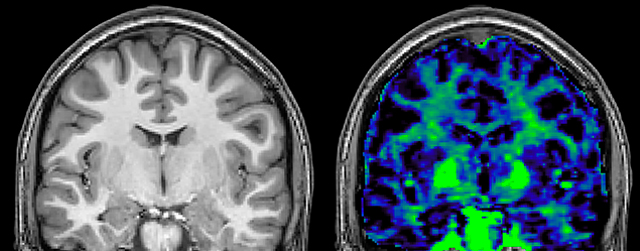

Myelin water imaging (MWI) is a breakthrough technique that was pioneered at UBC for measuring myelin content in the brain, in vivo. “Because the T2 time of water in myelin is much shorter than the T2 of water in the intraand extracellular spaces, we can separate out the myelin water signal.”

The techniques for measuring myelin have changed a lot over the years. “Since we are using the Elition, our myelin water images are much better. We're now acquiring 1 x 2 x 5 mm voxels and displaying at 1 x 1 x 2.5 mm. For a whole brain we can now measure the fraction of water in the myelin component in only about five or six minutes,” Dr. MacKay says.

of limiting MWI to the brain, even without the cerebellum, we can now spend about the same amount of time and scan the whole brain and the cervical spinal cord, which is a huge boost for us.” Dr. Rauscher says, “For MWI we perform 3D T2 with 32 or more echoes. This used to take a long time, but with Compressed SENSE we can decrease this to ten minutes for the whole head. Because of the large field of view (FOV) on the readout direction, we even get information from the brainstem, which we previously missed when we were using the GRASE approach. Having the whole head scan is nice because it has spatial resolution, orientation and FOV that are comparable to the standard 3D clinical MS scans, including the FLAIR and 3D T2, and a 3D T1 for brain volume.”

T1 - weighted

Myelin water imaging (echo 1)

With SENSE

With Compressed SENSE

Acquired resolution:

1 x 2 x 5 mm3

→

1.5 x 2 x 3 mm3

Number of echoes:

32 or 48

56

Echo spacing:

10 ms or 8 ms

7 ms

T1 - Weighted, Myelin Water Fraction Superimposed

Spinal cord coverage

Smaller, more isotropic voxels

Excellent detail in quantitative maps

Images courtesy of Adam Dvorak, Department of Physics and Astronomy, University of British Columbia